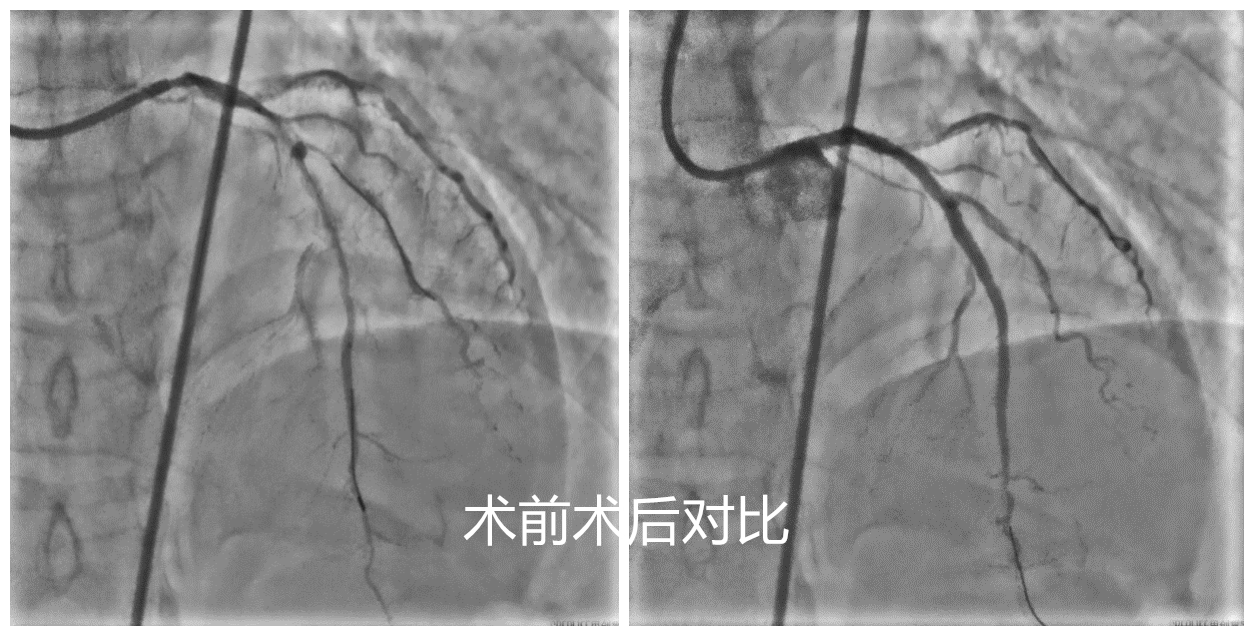

患者是59岁女性,1月前因“急性下壁心肌梗死”就诊于当地医院,行急诊PCI术(经皮冠状动脉介入治疗),造影结果显示右冠近段闭塞,前降支、回旋支近中段重度狭窄并弥漫性钙化,开通右冠后患者症状好转出院。但患者反复心绞痛发作,于是前往兰大二院进一步治疗。入院后,孙守刚主任医师团队详细评估病情后,发现患者冠脉严重钙化,其走行在胸部CT中清晰可见。经讨论后,决定对患者实施冲击波球囊导管成形术。术中碎裂前降支近中段0.88-1.24mm的点状及环形钙化病变后顺利植入支架,血管顺应性明显改善。术后患者心绞痛症状再未发作,病情平稳,现已治愈出院。